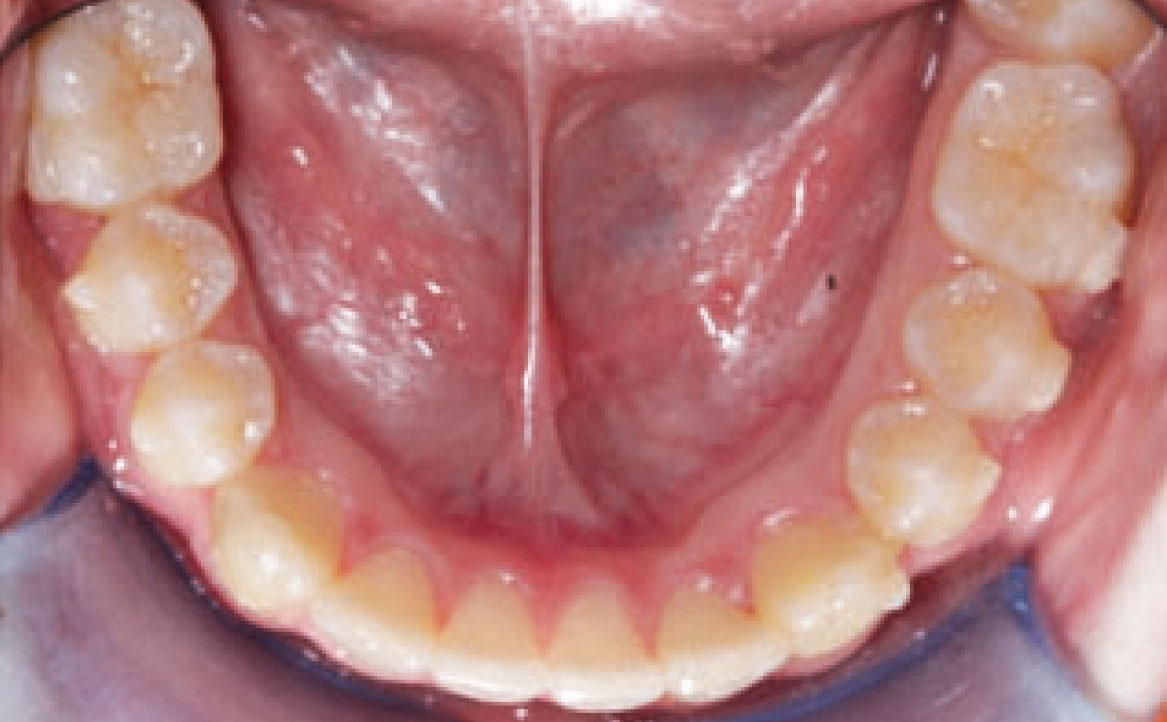

Dall’esame obiettivo intra orale si osservava una seconda classe canina destra e sinistra, una seconda classe molare destra e sinistra, e un diametro inter-canino e inter-molare ridotto sia in riferimento al mascellare superiore sia al mascellare inferiore (fig. 3A-3E).

A seguito del trattamento è stato osservato un miglioramento dell’igiene orale (fig. 5).